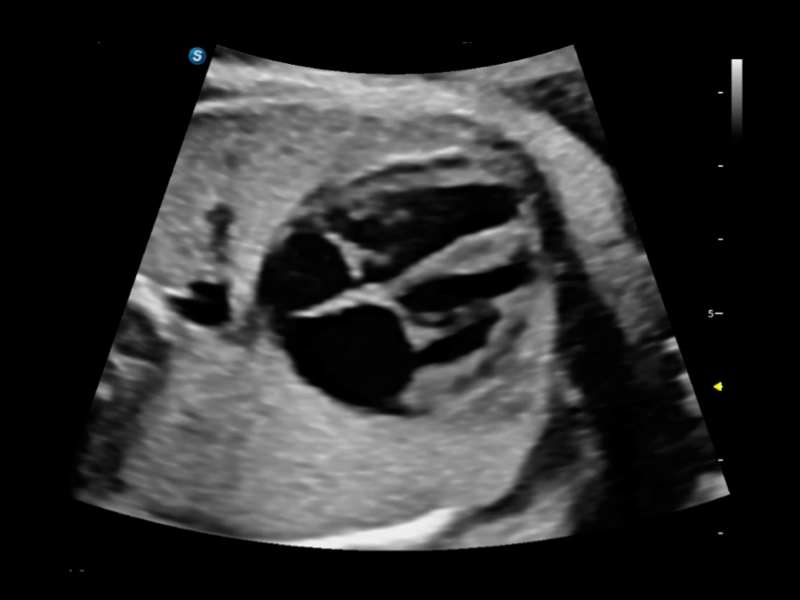

• S-Live Studio liefert eine brillante, realistische Hautvisualisierung in Echtzeit, indem es die Lichtausbreitung auf der Hautoberfläche simuliert und so die Tiefe und Authentizität des dreidimensionalen Bildes bereichert.